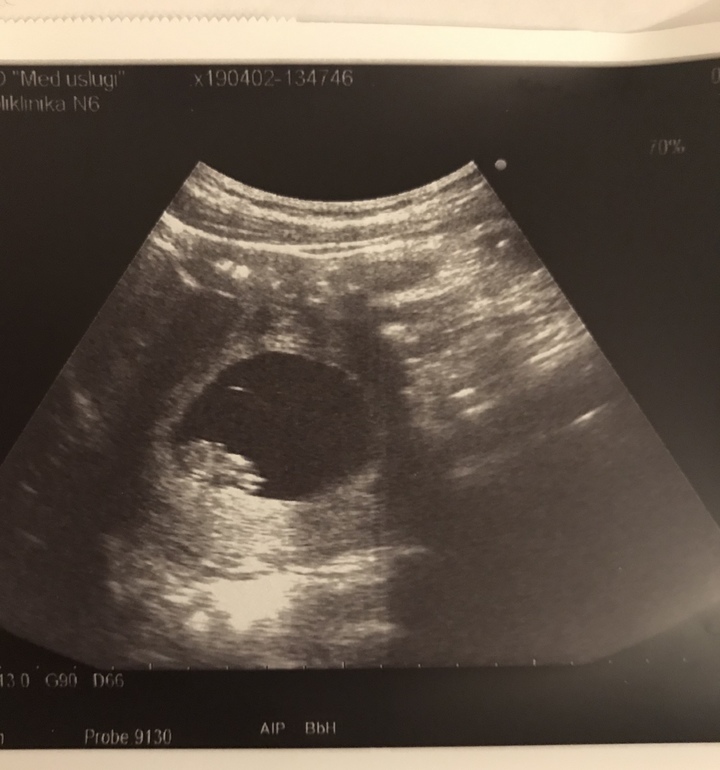

Увидел папочка своими глазами крохотульку, услышал сердечко, и наконец успокоился) Малыш соответствует сроку, КТР 22 мм, ЖМ 5,4 мм, чсс 156 уд/мин. Уже видно было что-то похожее на ручки-ножки, но аппаратура не экспертного класса конечно, хотя пока и этого достаточно. Узи уже делали абдоминально.